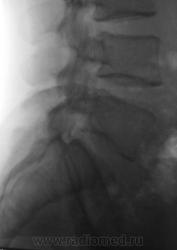

Пациент с болями в пояснице, направлен на рентгенологическое исследование поясничного отдела позвоночника.

задний спондилолистез L3,L4. сакрализация L5.признаки остеохондроза.аномалия тропизма L3-L4 справа ,L5 с обеих сторон.

При всем уважении к коллеге stovbav, лестничный микроретролистез L-2-L-3-L-4 может инициировать такие боли в спмне, что "мама, не горюй". А удлинение задне-нижних углов тел L-3,L -4 запросто могут оказаться косвенными признаками дорсальных протрузий диска..